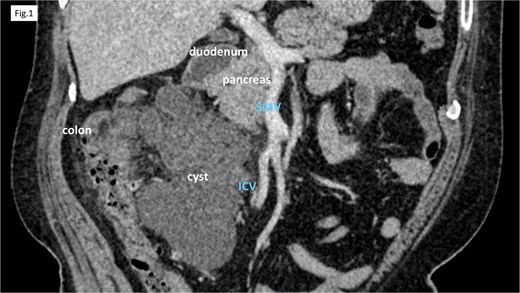

Computed tomography (CT) revealed cystic lesions located in the mesentery of the right colon, without apparent connection to the gastrointestinal tract (Fig. 1). Magnetic resonance imaging (MRI) confirmed the presence of multiple non-enhancing cystic lesions (Fig. 2). Radiological findings suggested that the cysts were confined to the mesentery of the ascending colon, delineated by the ileocolic artery and vein (ICA/V), the right margin of the superior mesenteric vein (SMV), and the right branch of the middle colic artery (MCA-rt) and accessory right colic vein (aRCV).

CT showed cystic lesions localized within the right colic mesentery.